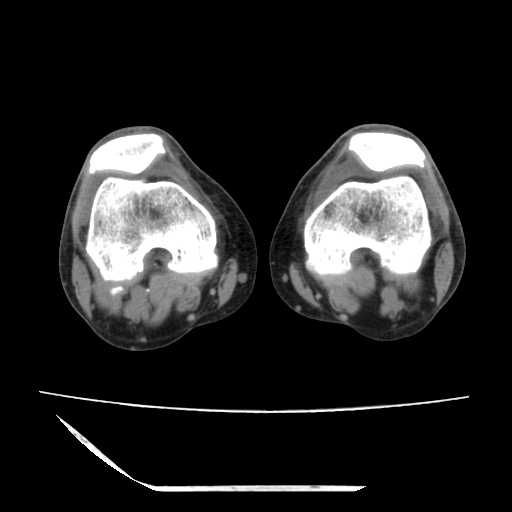

标题: CT13225:老年男性,左膝关节疼痛数月;请各位老师讨论。 [打印本页]

标题: CT13225:老年男性,左膝关节疼痛数月;请各位老师讨论。

骨质增生,骨性关节面硬化,关节积液,考虑退行性骨关节病

关节腔内少量积液,关节面退变。

双膝退变

骨质增生,骨性关节面硬化,关节间隙失常,关节积液,考虑退行性骨关节病.

骨质增生,骨性关节面硬化,关节积液,考虑退行性骨关节病。

这个病例诊断:退行性骨关节炎